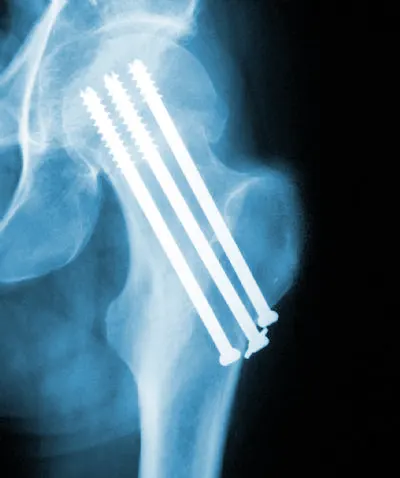

Cannulated screws are used in bone and joint surgery to repair breaks and to secure artificial implants which may be used to replace part or all of a joint.

Cannulated screw enable the performance of what are called percutaneous techniques, where a surgical procedure takes place through puncture holes in the skin rather than making a large open incision. This type of surgery may be used to treat a femoral neck fracture, where the ball-shaped head of the thigh bone breaks off at the narrow point, or neck, where it joins to the shaft. The operation can only be used in cases where the broken bone is still in place, to ensure that the head of the thigh bone has not had its blood supply disrupted and will remain alive after the screws have secured it in place.